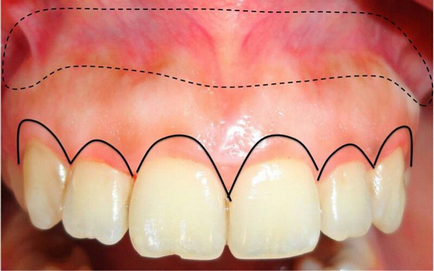

Az alábbi fotó, a szaggatott vonal jelzi a szövetet kivágtuk, és az összefüggő vonal - korrekció a gingivális kontúr. Így, amely egyesíti a két módszer lehet teljesen korrigálni gingivális mosollyal.